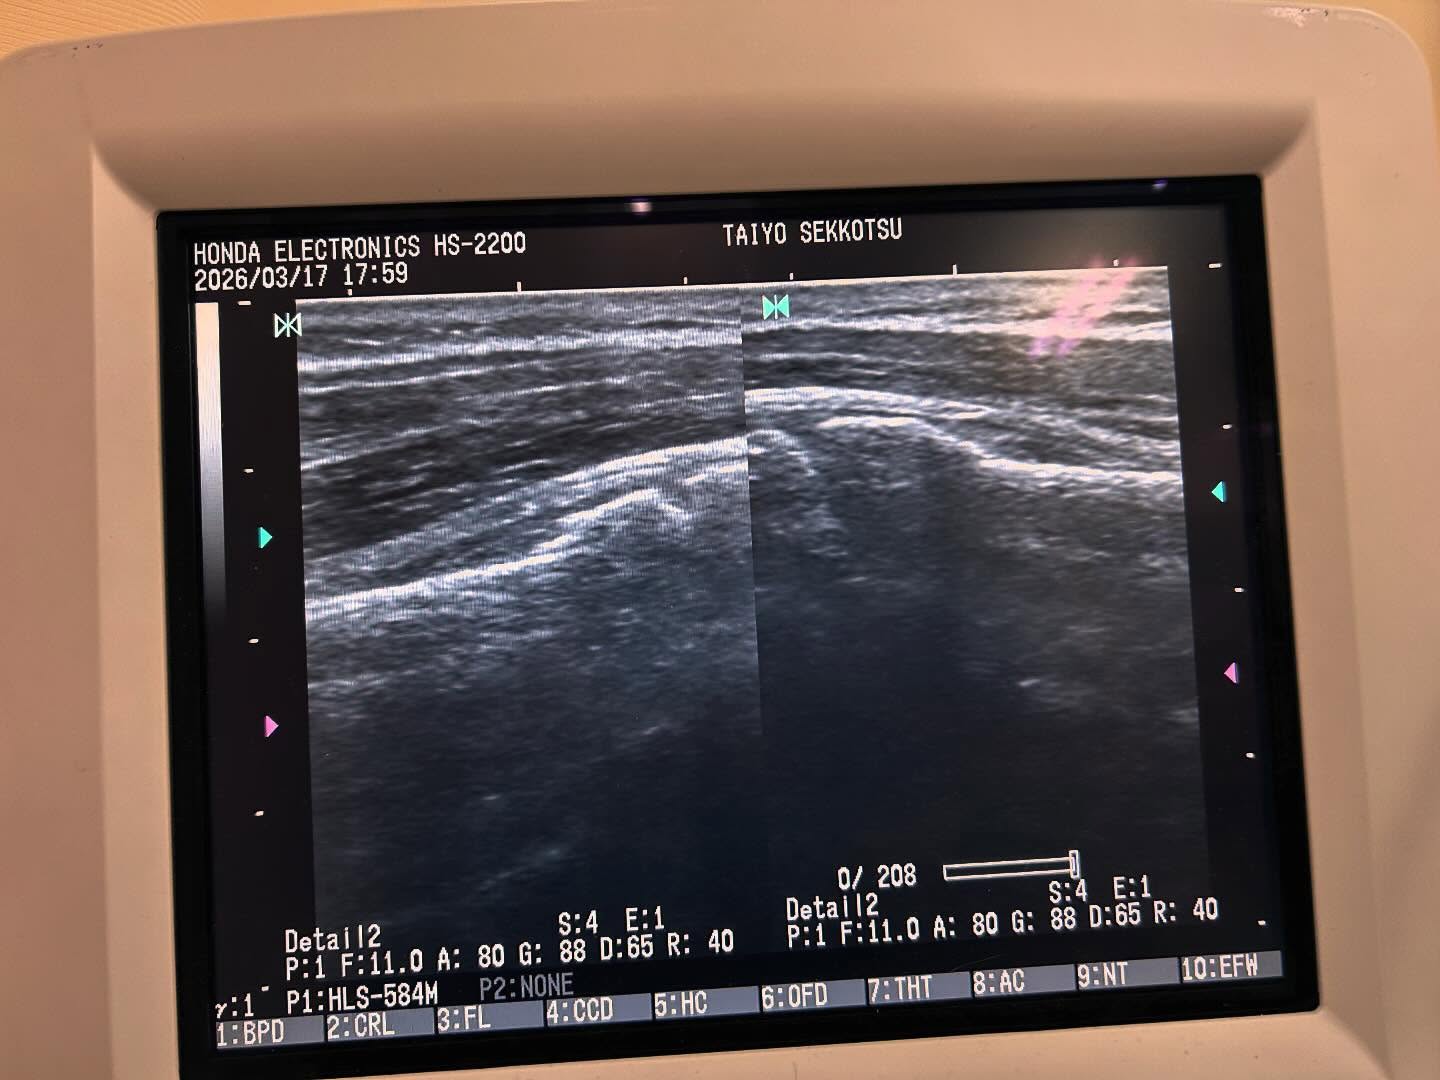

午後の診療にて

転倒した時に腕を突いて身体を支えた時に、左上腕が痛くなった、と訴え来院。

①痛みで、なかなか衣服の着脱が出来ない

②腕を動かすのがキツイ(困難)

③限局性の圧痛

④負傷の時間から2時間は経過している→その割に腫れが少ない。

もしかして…超音波画像観察装置にて、観察した結果

左上腕骨近位部の若木骨折疑い、と判断。

午後6時前のこの時間に、診療している病院やクリニック(整形外科を標榜する)はギリギリ受付してくれるかどうか?

応急手当てを施し、医科を受診してもらうよう話す。

最近は外傷も多く、骨折もいつもより多いな?!と思います。

卒業や入学の時期です。

気をつけてお過ごしください。

野田市には、整形外科で6年研修してきた(骨折、脱臼の整復・固定、リハビリも多々経験させて頂きました)。

そういうキッチリとした柔道整復師の、たいよう接骨院

すずきがいるじゃないか!